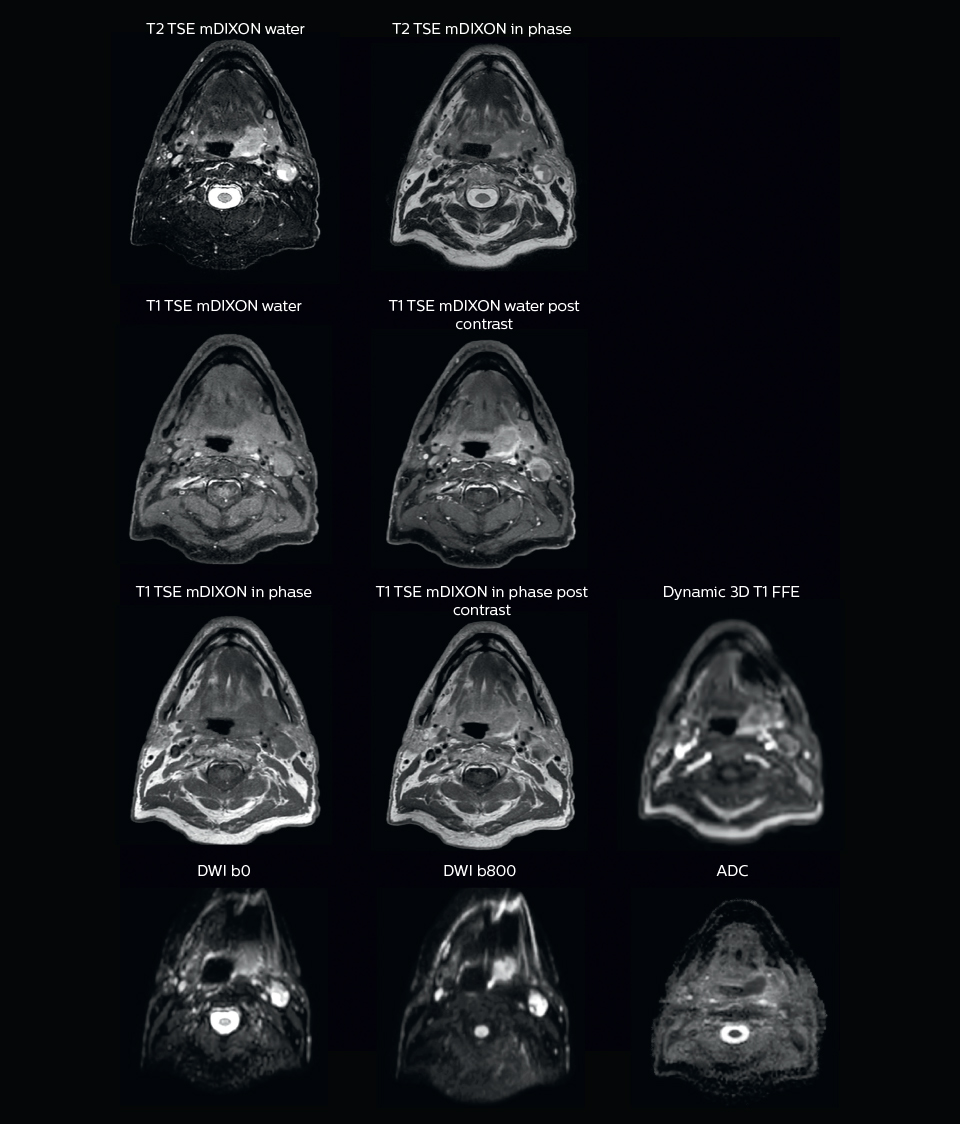

“We use pre- and post-contrast T1- and T2-weighted sequences with the fast and robust mDIXON method for fat suppression,” says Dr. Philippens. “Dynamic contrast-enhanced imaging is performed with high temporal resolution and low spatial resolution, to see the contrast agent uptake in the tumor. Diffusion weighted imaging is used qualitatively to see how the tumor extends into another structure, rather than for strict delineation.”

“In postoperative patients who have had tumor growth along the cranial nerves, we use T2-weighted gradient echo (FFE) on our 3.0T MR-RT scanner to show the nerves for target delineation and look to see if there is still tumor left.”

“In patients with a primary tumor in the head and neck area, we do use MRI in daily clinical radiation therapy practice to visualize the tumor and critical structures. This may be used to help sparing of critical structures, such as the parotid glands, submandibular glands, esophagus, optic nerves, brain stem and spinal cord [7]. And postoperatively we scan patients that have tumor growth along the cranial nerves for target delineation,” says Dr. Philippens.

“Because of the challenges posed by CT-MRI coregistration in this area with many degrees of freedom for motion, we image these patients in a radiotherapy mask. However, one disadvantage of using the mask is that a regular head and neck coil cannot be used; a dedicated coil solution would be needed for imaging with a mask.

For this we make use of flexible coils that we position close to the target area. This setup can also be combined with the anterior coil for a larger coverage and enhanced SNR.”